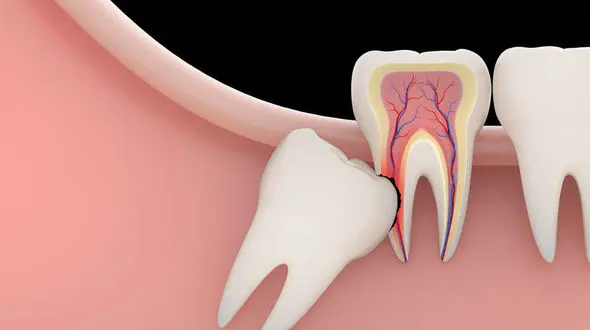

سلامت رکنا : بیشتر درد دندان عقل به این دلیل رخ می دهد که لثه اطراف آن در اثر کاهش تمیز کردن عفونی می شود.

رکنا: دندان عقل چون سبب بهم ریختگی فرم دندان ها می شود بهتر است کشیده شود.